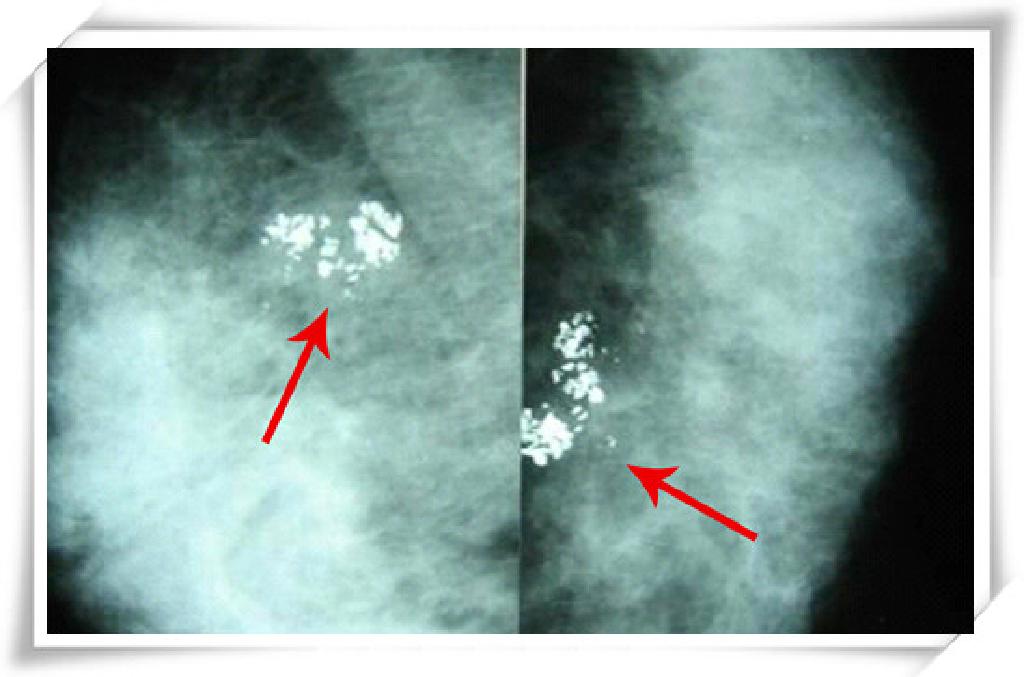

钼靶,极软X线:波长较长,能量较低,以此扩大乳腺组织之间的X线吸收差异,增强图像的对比。其优点是可清晰显示乳腺各层组织,可以发现乳腺增生、各种良性肿廇、恶性肿瘤以及乳腺组织结构紊乱,如“火眼金睛”般观察到小于0.1毫米的微小钙化点及钙化块。

多发微细钙化灶,呈簇状分布,无肿块。

手术病理证实:右乳导管原位癌